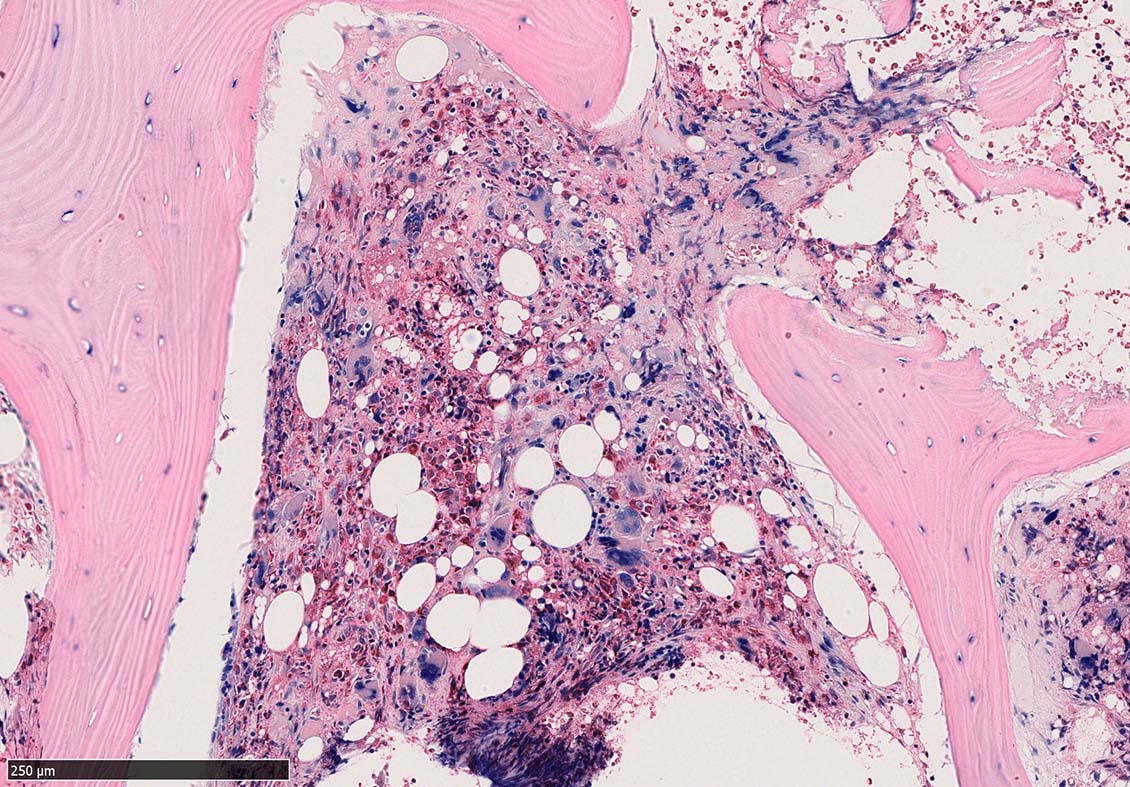

Case02; Meylofibrosis, overt fibrosis

77year-old female. 40歳時polycythemia veraと診断されていた.

[注] この症例は詳細は不明であるが, 過去にPVと診断されているため, PVに伴う二次性のmyelofibrosisの診断になる.

黒染する弾性線維の増生のほか, 赤く染まる膠原線維の増生が確認される. MF-2 fibrosis. 鍍銀染色の核染色をすると膠原線維の赤染がわからなくなるので行わない.